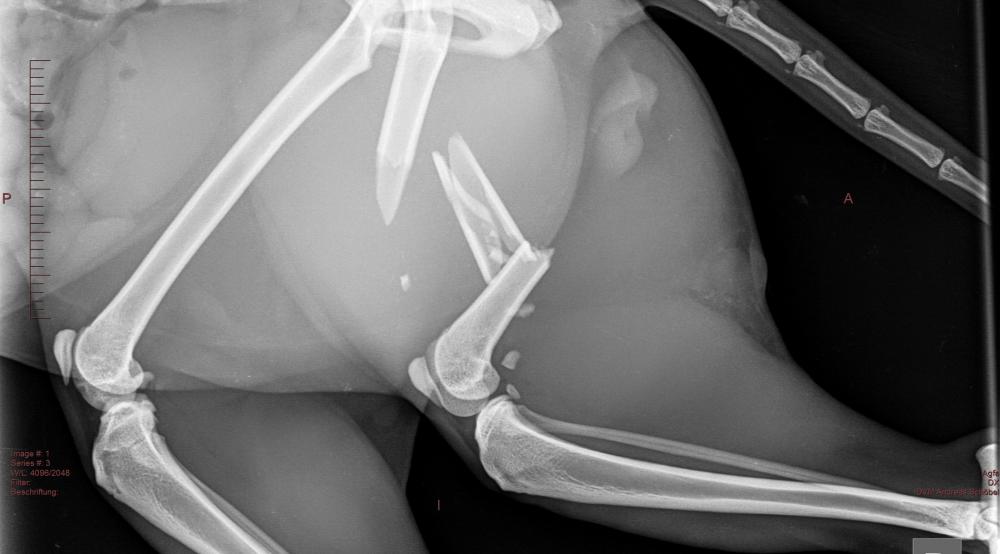

Viele Patienten werden in unserer Praxis vorstellig, weil sie eine Lahmheit zeigen. Oft ist bei dem Betreten des Behandlungsraumes noch nicht klar, welches Gelenk oder welcher Knochen betroffen ist. Manchmal ist sogar unklar ob und wenn ja um welche Gliedmaße es sich handelt. Auch Kopf, Wirbelsäule, Schultern und Becken können Grund für einen „unrunden Gang“ sein. Manchmal verbirgt sich aber auch kein orthopädisches sondern ein internistisches Problem dahinter. Hunde aber auch Katzen leiden im Alter außerdem oft an Arthrosen.

Um Klarheit zu schaffen wo das Grundproblem ihres Lieblings liegt, legen wir großen Wert auf eine vollständige Allgemeinuntersuchung und eine spezielle Lahmheitsuntersuchung mit Gangbildanalyse. So wird festgestellt, wie dem Patienten optimal geholfen werden kann und ob Ruhighaltung und Schmerzmittel ausreichen oder ob weitere Diagnostik wie Röntgen, Ultraschall und Labor oder sogar eine Operation nötig werden.